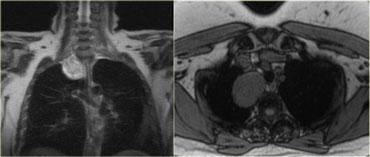

Ví dụ:

Bờ bên và bờ trên của tổn thương trung thất này hiện rõ ràng, có nghĩa là tổn thương được bao quanh bởi mô phổi. Tổn thương kéo dài lên trên xương đòn và do đó được xác định là nằm ở trung thất sau.

Bên trái là hình ảnh MRI của cùng bệnh nhân.

Kết quả cho thấy đây là u bao thần kinh schwannoma.